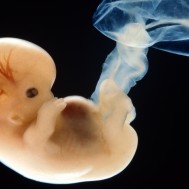

Baby: Week 6

You’re now making spontaneous movements, and can twitch your trunk and limb buds

Each day, changes make you more recognisable as a small person just like you. Now your lungs are forming![1] Brain function, as measured by EEG waves, can be recorded within days.[2] Nerve cells in the brain are connecting, forming primitive neural pathways. Your hands can bend at the wrist, and webbing is disappearing from your feet. Your tail is just about gone. Tastebuds are forming on your tongue.[3] You’re now making spontaneous movements, and can twitch your trunk and limb buds.[4]